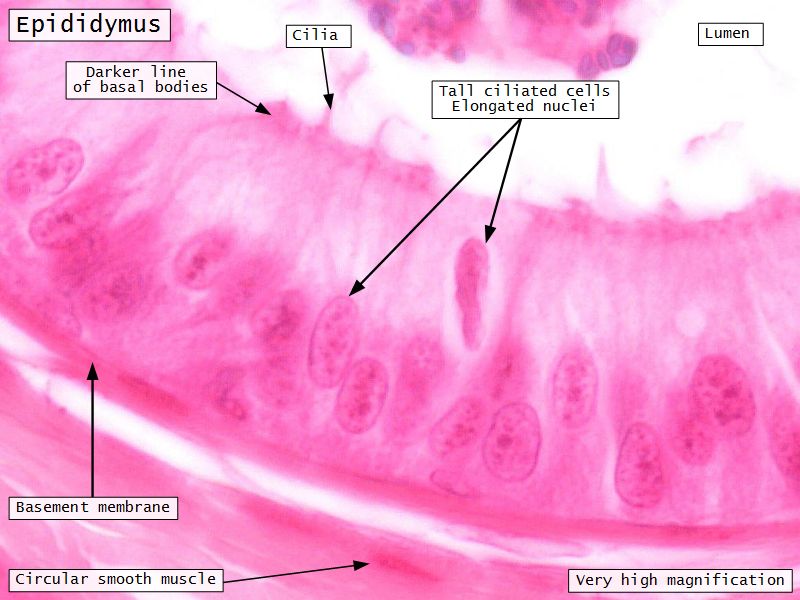

Epididymus

- Simple ciliated columnar epithelium

- Tall ciliated cells

- Elongated nuclei away from BM

- Low absorptive cells

- Spherical nuclei close to BM

- Surrounded circular smooth muscle